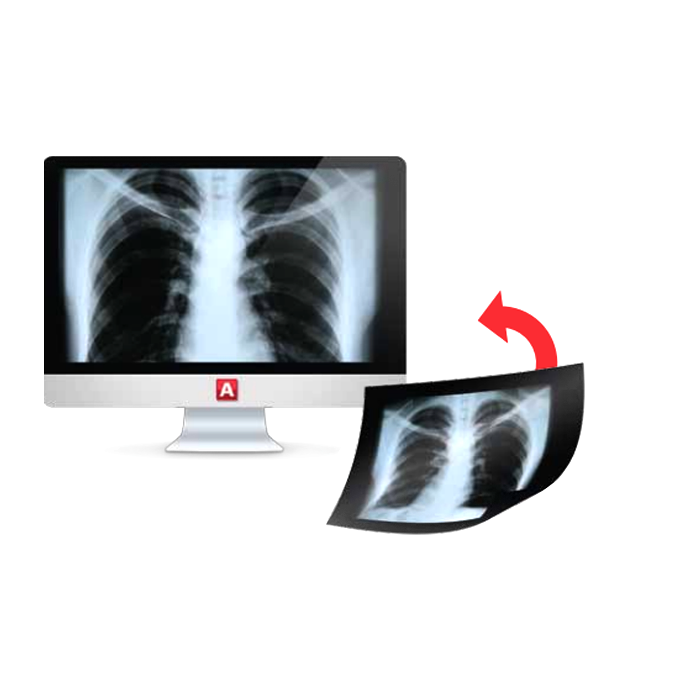

- Работа с изображениями: Автоматический прием снимков с любого DICOM-совместимого оборудования (КТ, МРТ, рентген, УЗИ и др.), организация единого защищенного архива.

- Снижение операционных расходов: Отказ от пленки и химикатов, экономия на физических носителях и площадях для архива.